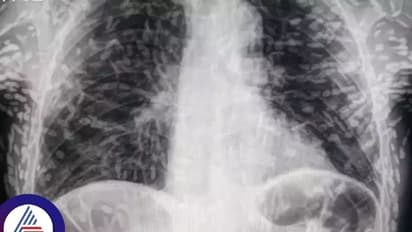

ಆರೋಗ್ಯ (Health) ಸರಿಯಿಲ್ಲವೆಂದು ಆಸ್ಪತ್ರೆಗೆ ಬಂದ ರೋಗಿಗೆ ವೈದ್ಯರು ಎಕ್ಸ್-ರೇ ತೆಗೆದಾಗ ಆಘಾತಕಾರಿ ವಿಚಾರ ಪತ್ತೆಯಾಯಿತು. ಬ್ರೆಜಿಲ್ನ ಸಾವೊ ಪಾಲೊದಲ್ಲಿರುವ ದಾಸ್ ಕ್ಲಿನಿಕಾಸ್ ಬೊಟುಕಾಟು ಆಸ್ಪತ್ರೆಯ ಅಭ್ಯಾಸಿ ಡಾ.ವಿಟರ್ ಬೋರಿನ್ ಪಿ. ಡಿ ಸೋಜಾ ಅವರು ಟ್ವಿಟರ್ನಲ್ಲಿ ಹಂಚಿಕೊಂಡ ನಂತರ ಸ್ಕ್ಯಾನ್ಗಳ ಫೋಟೋಗಳು ವೈರಲ್ ಆಯಿತು.

ಪರೀಕ್ಷೆಗಳು ಮತ್ತು ಸ್ಕ್ಯಾನ್ಗಳು ಹಂದಿಮಾಂಸದಿಂದ ದೇಹ (Body)ದಲ್ಲಿ ಹುಳುಗಳು ಉಂಟಾಗಿರುವುದ್ನು ಬಹಿರಂಗಪಡಿಸಿತು. ವ್ಯಕ್ತಿ ಅಂಗಾಂಶದ ಸೋಂಕಿನ ಸಿಸ್ಟಿಸರ್ಕೋಸಿಸ್ನಿಂದ ಬಳಲುತ್ತಿರುವುದು ಪರೀಕ್ಷೆಯಿಂದ ತಿಳಿದುಬಂತು. ಇದು ಸಾಮಾನ್ಯವಾಗಿ ಆಹಾರ (Food) ಸೇವನೆಯಿಂದ ಅಥವಾ ಮಾನವನ ಮಲದಿಂದ ಟೇಪ್ ವರ್ಮ್ಗಳ ಮೊಟ್ಟೆಗಳಿಂದ ಕಲುಷಿತಗೊಂಡ ನೀರನ್ನು ಕುಡಿಯುವುದರಿಂದ ಉಂಟಾಗುತ್ತದೆ ಎಂದು ರೋಗ ನಿಯಂತ್ರಣ ಮತ್ತು ತಡೆಗಟ್ಟುವಿಕೆ ಕೇಂದ್ರಗಳು (CDC) ಹೇಳುತ್ತದೆ:

ಅವರ ಪ್ರಮುಖ ಅಂಗಗಳ ಸಂಪೂರ್ಣ ಸ್ಕ್ಯಾನ್ ಮಾಡಿದಾಗ, ಫಲಿತಾಂಶಗಳು ಆಸ್ಪತ್ರೆಯ ವೈದ್ಯಕೀಯ ಸಿಬ್ಬಂದಿಯನ್ನು ಆಘಾತಗೊಳಿಸಿದವು. ವ್ಯಕ್ತಿಯ ಮೆದುಳು, ಎದೆ ಮತ್ತು ಶ್ವಾಸಕೋಶದಲ್ಲಿ 700 ಟೇಪ್ ವರ್ಮ್ಗಳಿವೆ ಎಂದು ಸ್ಕ್ಯಾನ್ಗಳು ಬಹಿರಂಗಪಡಿಸಿದವು.